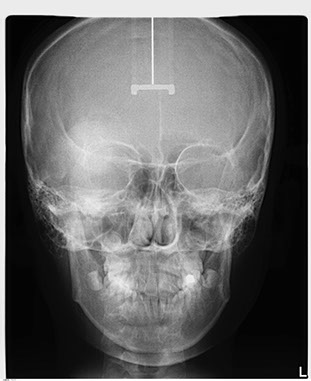

正頭顱X光攝影(P-A view) 是一張由後腦往前投射拍攝正面觀的頭顱影像(Posteroanterior view),主要評估臉部的左右對稱性,並非每位矯正患者都需要此張影像,如果從外觀看似左右臉型不太對稱者,醫師就可能要求做此攝影檢查。